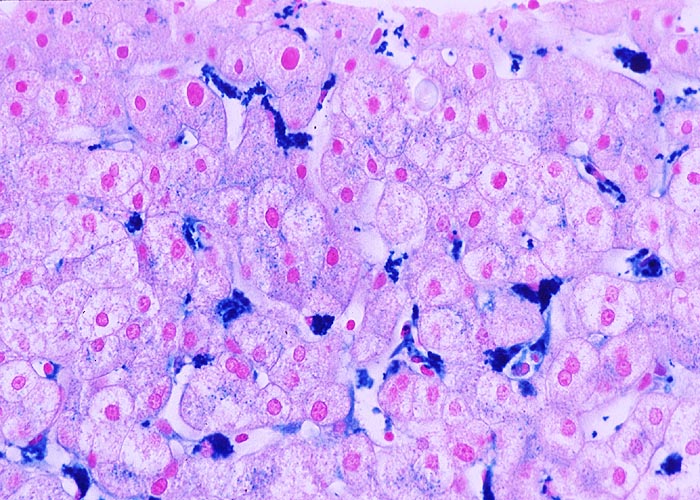

PathoPic – image database / PathoPic ID 975 - Sternzellsiderose

Sternzellsiderose

Artefakt / Fremdkörper / Pigment

Leber

Leber, Gallenwege, Pankreas

In der Eisenfärbung werden die Hämosiderin speichernden Kupffer'schen Sternzellen in den Sinusoiden gut sichtbar. In den Hepatozyten finden sich nur sehr geringe feinkörnige Eisenpigmentablagerungen.

Zahlreiche Bluttransfusionen wegen hämatologischer Erkrankung.

Histologie